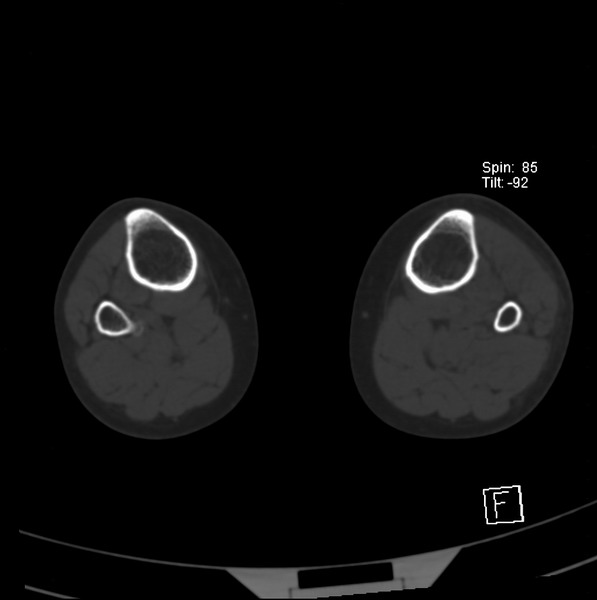

标题: CT21917:右腓骨小头是否骨软骨瘤? [打印本页]

标题: CT21917:右腓骨小头是否骨软骨瘤?

女、43.

不是骨软骨瘤,“牵拽征”,正常变异。有平片吗?

正常变异,“牵拽征”,比目鱼肌牵拽.